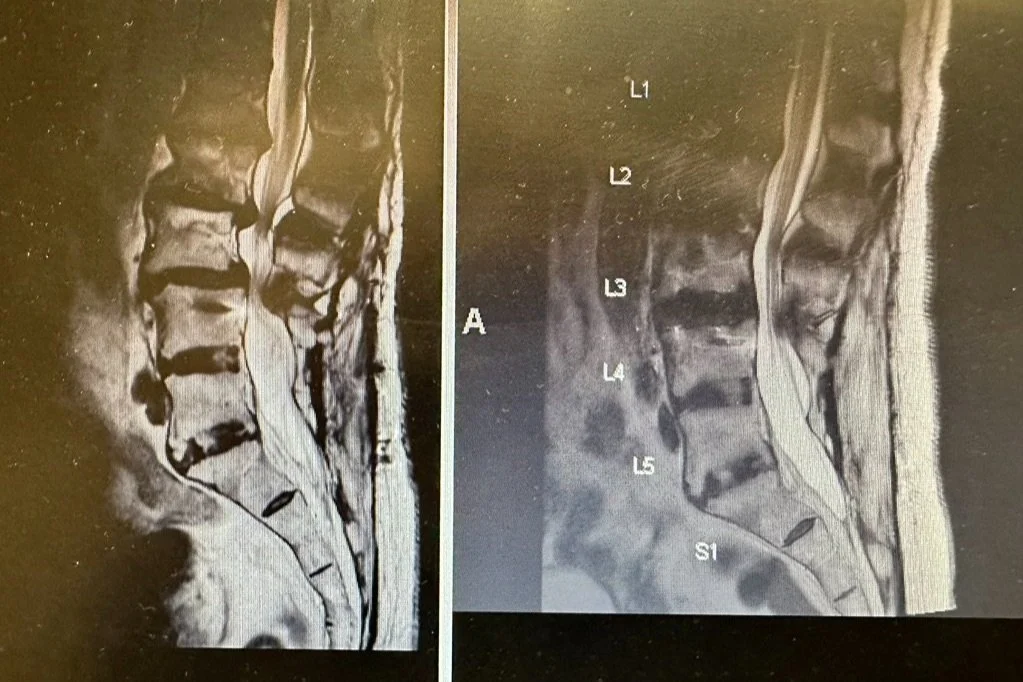

Case examples